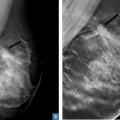

De plus, si cette technique a peu d’intérêt dans l’identification et la caractérisation d’un foyer de microcalcifications, elle permet de mieux évaluer les contours d’une lésion potentielle et d’individualiser une distorsion architecturale. En revanche, elle fournit peu d’arguments spécifiques quant au caractère malin (carcinome canalaire invasif, tubuleux) ou bénin (cicatrice radiaire et surtout postopératoire) de cette dernière.

Dans les asymétries de densité, on peut identifier des signes associés de distorsion architecturale (spicules épais et courts sans centre dense ou alors de petite taille) orientant vers la malignité.